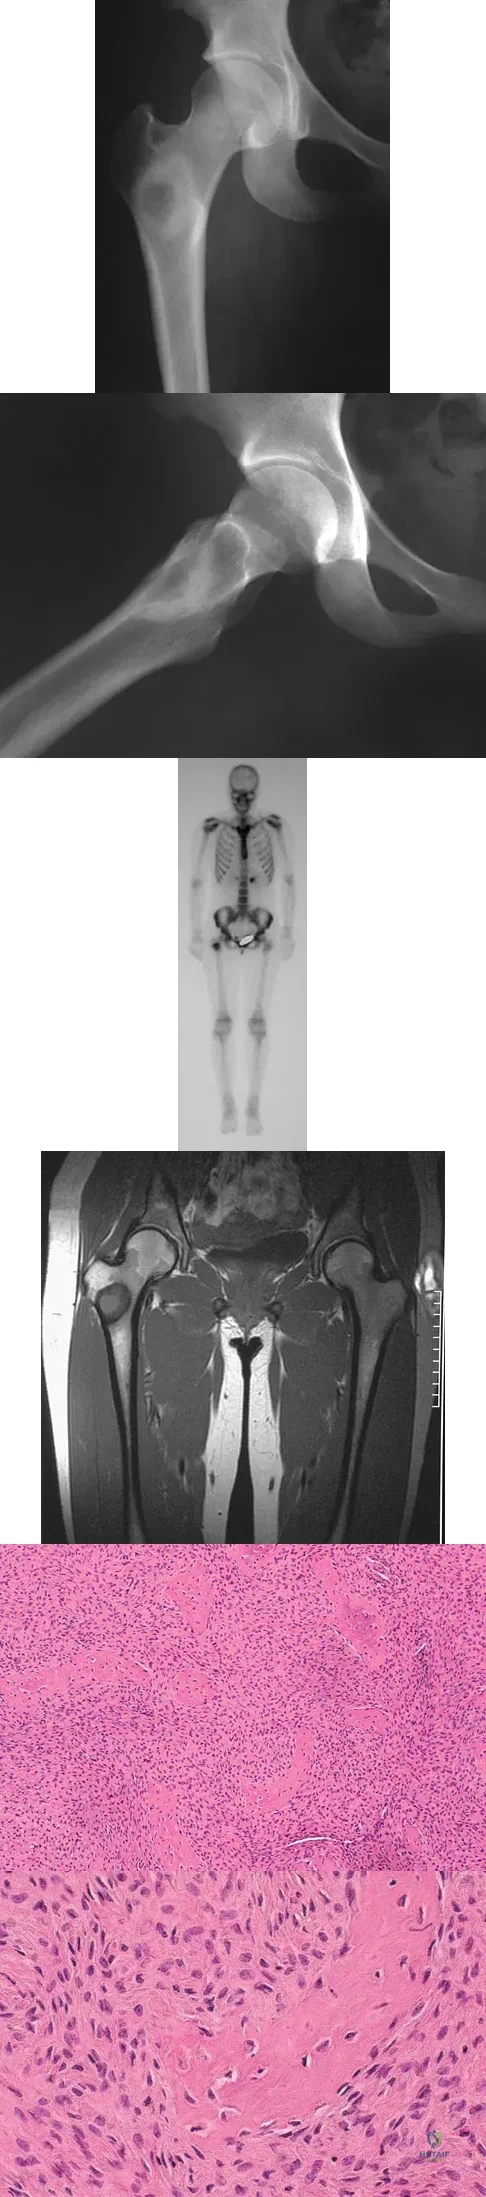

A 35-year-old man reports the development of a painful 2-cm nodule on his dorsal wrist over the past 3 years. A surgeon excised the lesion with a presumptive diagnosis of a ganglion cyst. Histology sections from the excision are shown in Figures 11a and 11b. What is the most likely diagnosis?